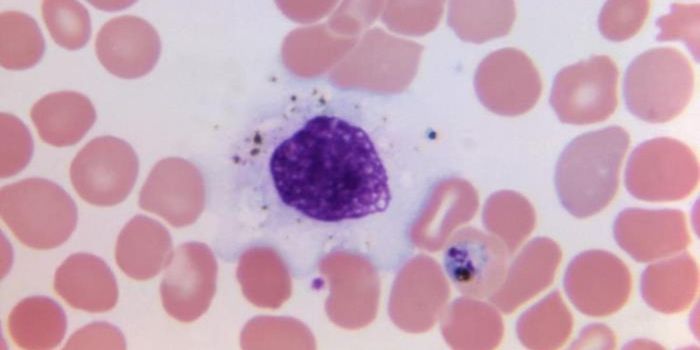

JUL 08, 2021Genetics & GenomicsChildren with Down syndrome have a significantly higher likelihood myeloid leukemia occurring in the first five years of ...